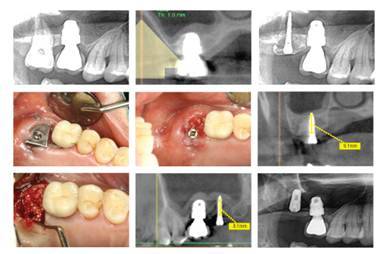

BOSS 시스템 임상적용 사례

▼BOSS Abutment의 임상적용

하악 좌측 제2소구치와 제2대구치에 오랜 기간 동안 가철성 의치 장착으로 인한 수평골 위축과 부착치은 소실 소견을 보인다. 임플란트 식립을 위한 치조골은 충분하므로 임플란트를 식립하고 BOSS Abutment를 체결해 골이식술을 하고 Teflon Sheet를 고정했다. 3주 치유기간이 지난 후 시트를 제거하고 Healing abutment를 연결했다. 3개월 후 임플란트 보철을 위한 인상채득을 실시, 충분한 폭경의 치조골과 부착치은이 재생됐다.

▼BOSS Screw의 임상적용·수직방향으로 식립

상악 좌측 제2대구치의 심한 동요도로 발치를 하였으나 잔존 치조골량이 부족해 임플란트를 식립할 수 없어 BOSS Screw를 발치와 중앙에 식립하고 골이식을 한 후 티타늄 시트를 고정했다. 4개월 치유기간이 경과하고 임플란트 식립을 했다. 이때 아직 발치와의 표면에는 골재생이 불완전하였으나 내부에는 임플란트 고정을 위한 골질이 갖춰져 고정력 25Ncm로 식립했다. 이로 인해 치조골이 충분한 높이와 폭경으로 골재생이 이뤄져 상악동 골이식이 추가로 필요하지 않았다.

▼BOSS Screw의 임상적용과 고찰-수평방향으로 식립

상악 좌측 제2소구치와 제1대구치 및 제2대구치가 발거 된지 수년이 경과해 협측 치조골이 심하게 흡수된 상태였다. 임플란트 식립 후에 협측골 노출이 심해 BOSS Screw를 협측방향으로 임플란트 사이에 하나를 고정하고 골이식을 시행했다. 치유기간 4개월 후 보철을 위한 2차수술에서 협측에 폭경 4.3㎜의 신생 골조직이 재생되었음을 알 수 있었다.